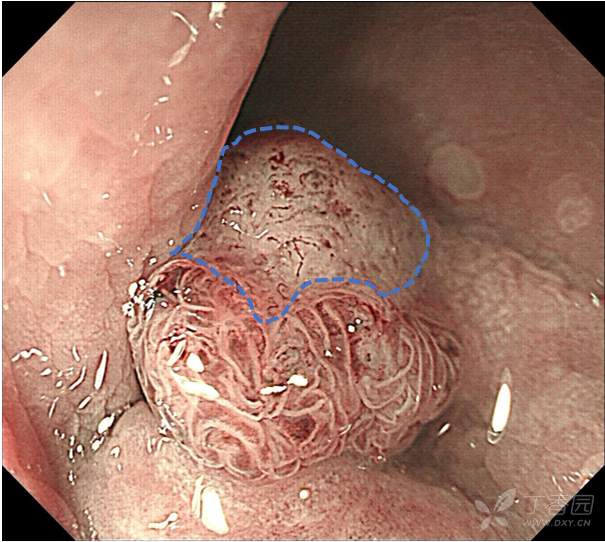

专注早癌诊断,从整体形态到微观表面,详细的判断:JNET、Pit pattern、浸润深度?

这是在跟老师发现的一例病人,在发现病人之后,通过不同的方法,比如NBI、放大、化学染色,对这个病变通过不同的角度,从宏观到微观细致的观察,详细的分析,以便于大家能够更好的理解:

一、pit pattern 分型的实际具体的形态是什么样子的?

二、JNET分型的特点和细微差别又是什么?

三、不同形态的病变,不同的分型的相应形态下对应的病理状态是什么?